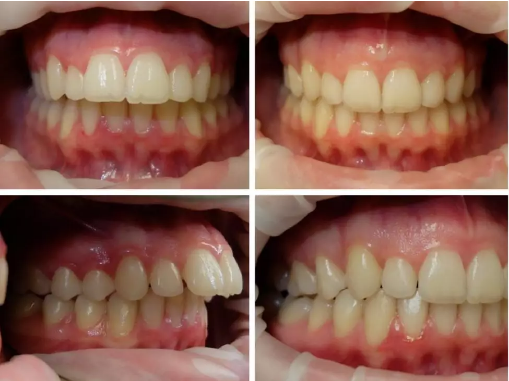

CASE 2

关键词

过咬合、凸嘴

这个是我们常说的龅牙(天包地),除了上排牙突出之外其他牙齿也很整齐没毛病。

这个妹妹也是拔掉了左右两颗第一前臼齿,把整排上牙往后推,总共是35个牙套,时长10个月,效果显著。

幅 35 10 月

CASE 3

地包天、虎牙突

这是一个地包天的案例,其实从侧面脸来看不是特别明显,但是牙齿可以明显看到咬合状态下是下牙比上牙前,张嘴不好看。

这是一个小女生,这种地包天的程度不算严重,没有拔牙,一共40个牙套,14个月完成~

其实我们做过很多地包天的案例都没有拔牙的~也有少数cases是比较严重的地包天,需要拔掉下排两颗牙齿把下排推进去很多。比如下面这个姑娘。

幅 40 14 月